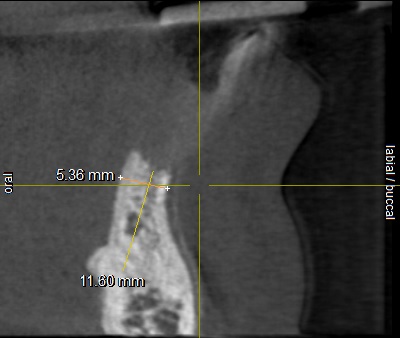

Edit Record Check our patient data records. Add patient information Patient Info Profile picture Last Name First Name Middle Name Birthdate Age Street Barangay City Country Zip Code Contact number Email Procedure 01/30/21 ICF - check up Feb 8,2021 - Implant 11/03/22- OP/OZONE/PAD feb,20,2021- removal of suture march 31,2021- LC 11 & 21 07/31/21 repair 41 zirconia resto 36CAOH/46 CAOH/43/34 OP June 4,2022 - OP / Xray 05/13/23- OP(Moderate); xray; ozone Oct 1 2023 op with air polisher noticed gum recession Removal of fiber splint on 42/43 05/07/24 Air polisher Xray OP 06/15/24 connective tissue graft harvested side: upper right quadrant w/ suture- monofilament absorbable 4/0 donor site: implant #41/32 buccal and lingual combination of monofilament absorbable 4/0 and nylon 6/0 non absorbable 06/22/24 check up 06/29/24 suture removal File raposa_donna_kelly_3.jpg File 2 raposa_donna_kelly_2.jpg File 3 raposa_donna_kelly_1.jpg File 4 donna_kelly.jpg File 5 june_42022.jpg File 6 raposa_donna.jpg File 7 raposa_donna_02.jpg File 8 img_2831.jpg File 9 File 10 File 11 File 12 File 13 File 14 File 15 File 16 File 17 File 18 File 19 File 20 Retain Record Retain Record Yes No Save Your Changes